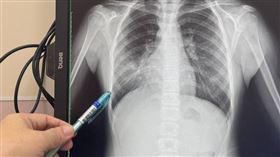

孩童染黴漿菌病例增 這些症狀出現快就醫

台中大甲李綜合醫院發現,近來兩周小兒科門診的孩童,罹...